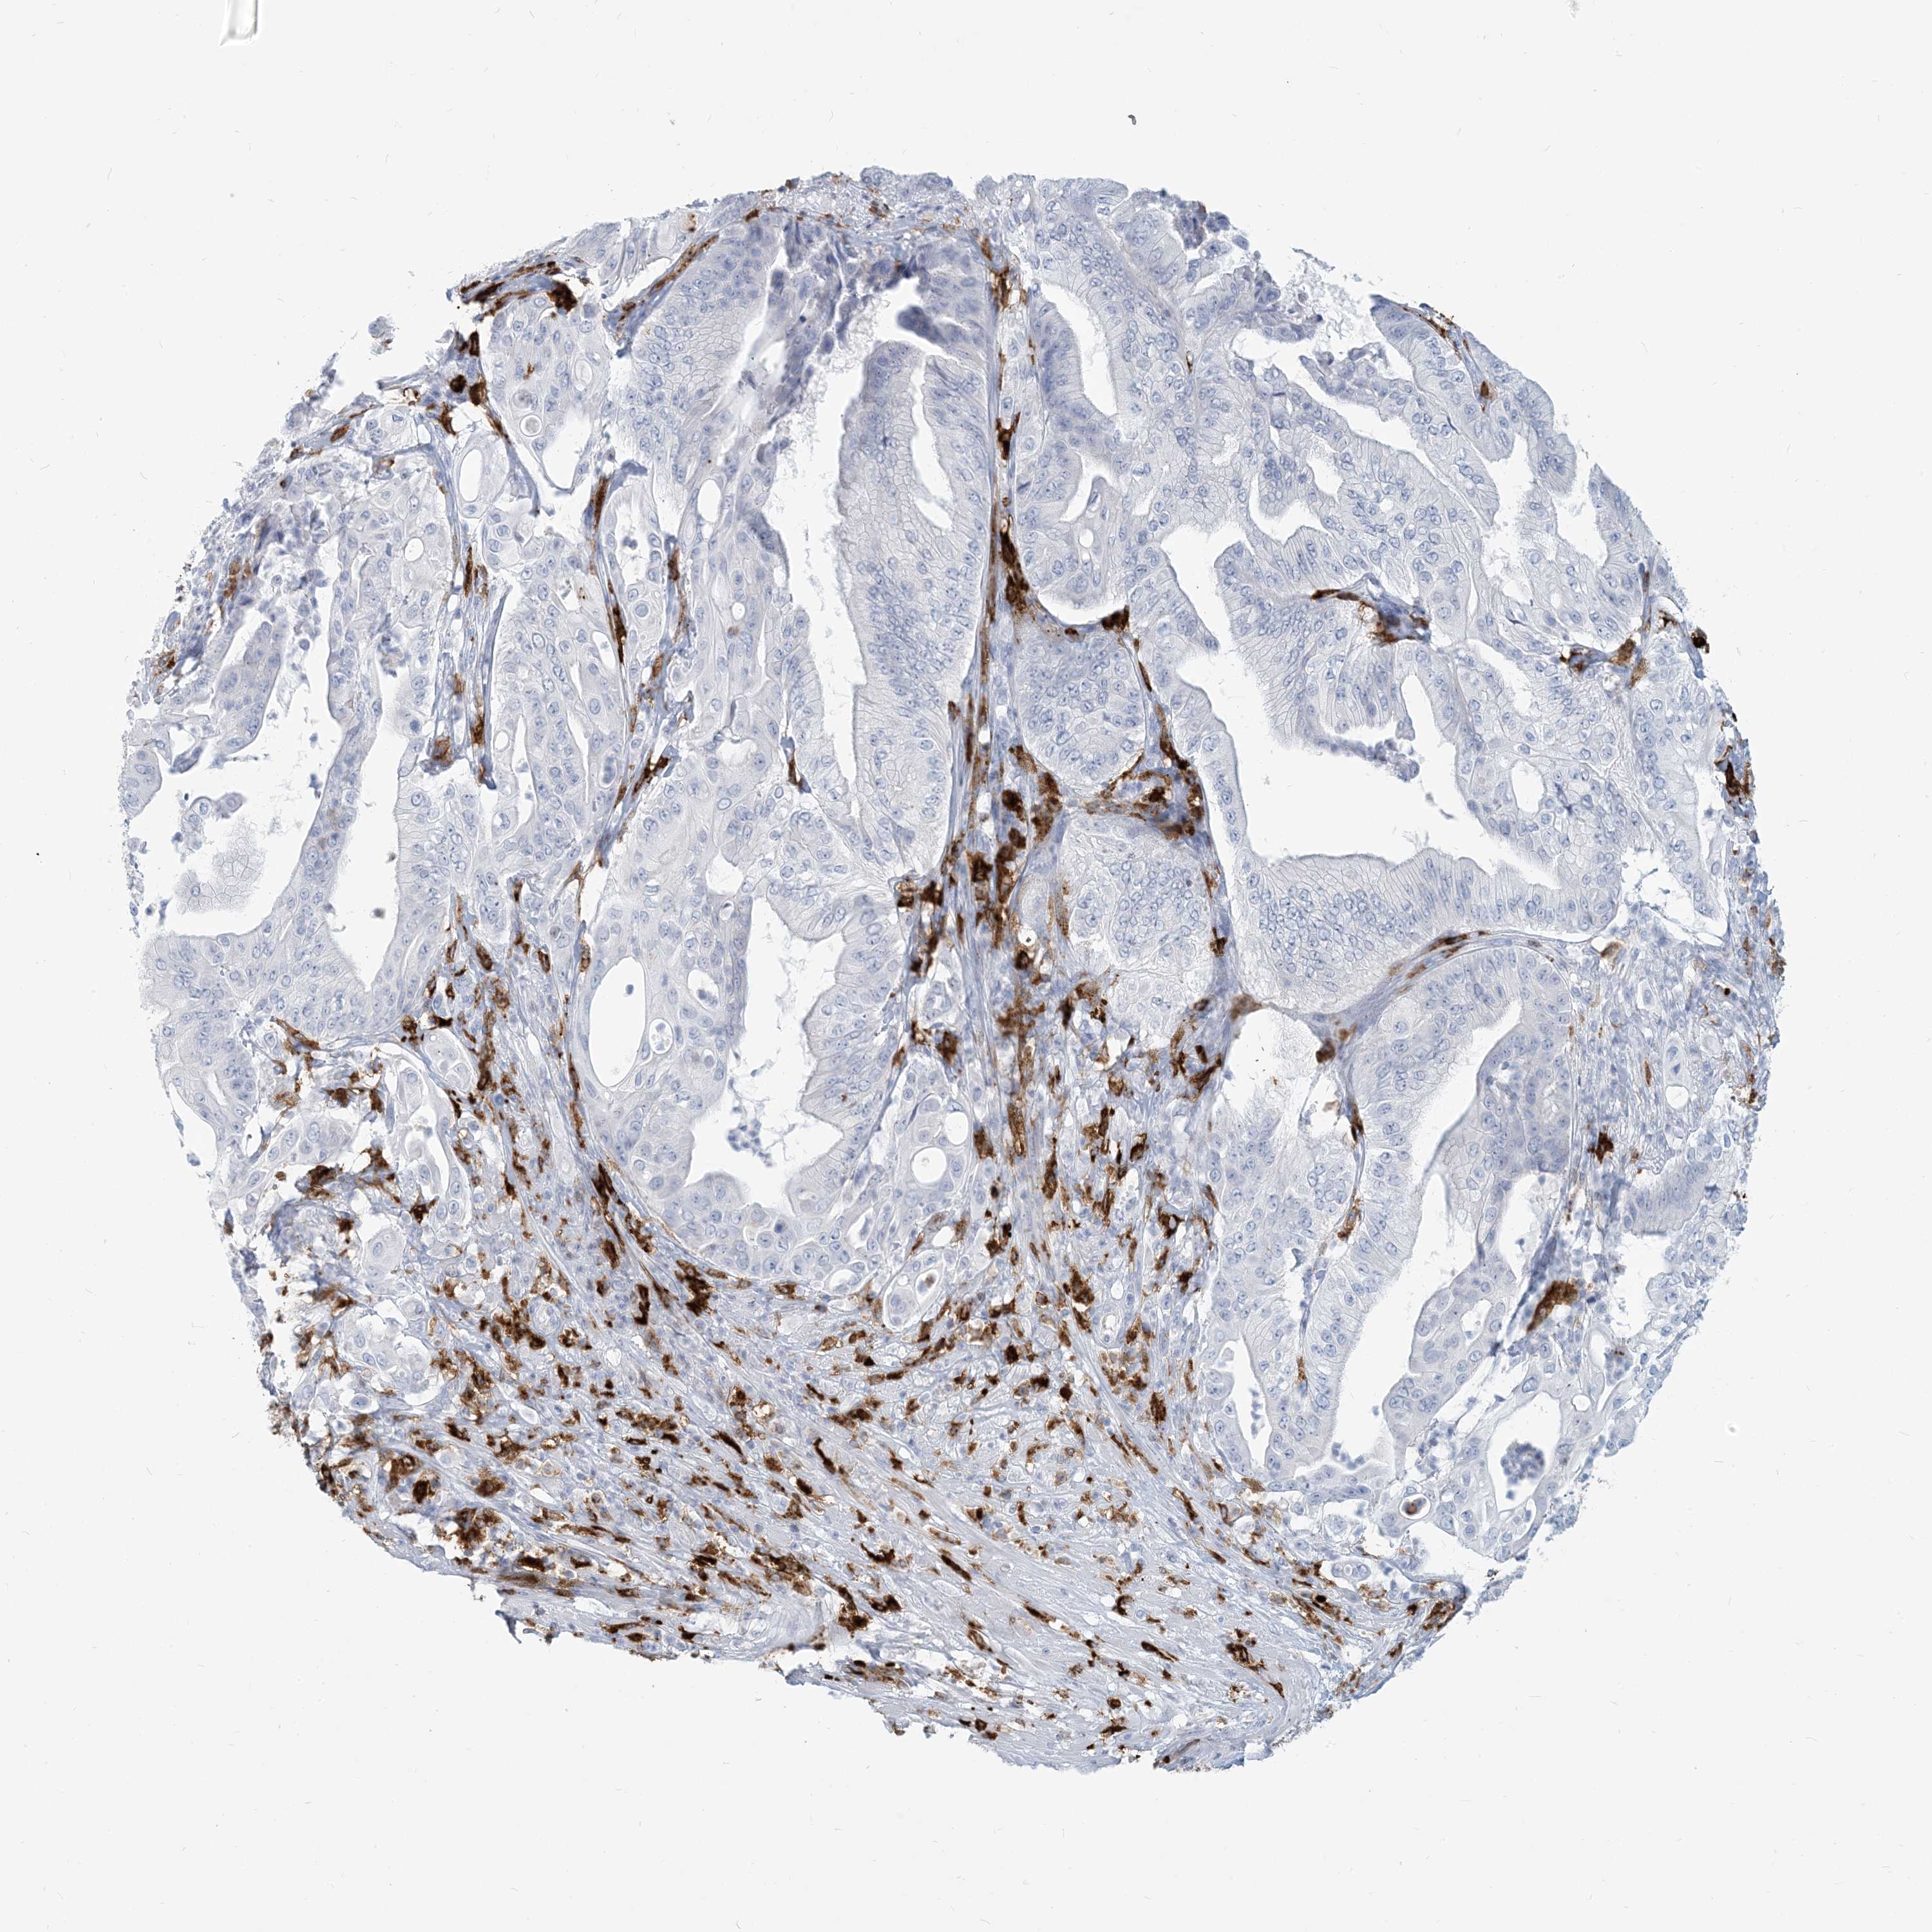

PANCREATIC CANCER - Protein expressioni

A mouse-over function shows sample information and annotation data. Click on an image to view it in a full screen mode. Samples can be filtered based on level of antibody staining by selecting one or several of the following categories: high, medium, low and not detected. The assay and annotation is described here.

Note that samples used for immunohistochemistry by the Human Protein Atlas do not correspond to samples in the TCGA dataset.

Antibody stainingi

Antibody staining in the annotated cell types in the current human tissue is reported as not detected, low, medium, or high, based on conventional immunohistochemistry profiling in selected tissues. This score is based on the combination of the staining intensity and fraction of stained cells.

Each image is clickable and will lead to virtual microscopy that enables deeper exploration of all samples and also displays staining intensity scores, fraction scores and subcellular localization as well as patient and tissue information for each sample.

Antibody HPA043151

Antibody CAB015400

Antibody CAB034021

Staining

High

Medium

Low

Not detected

Intensity

Strong

Moderate

Weak

Negative

Quantity

>75%

75%-25%

<25%

None

Location

Nuclear

Cytoplasmic/membranous

Cytoplasmic/membranous,nuclear

Adenocarcinoma, NOS